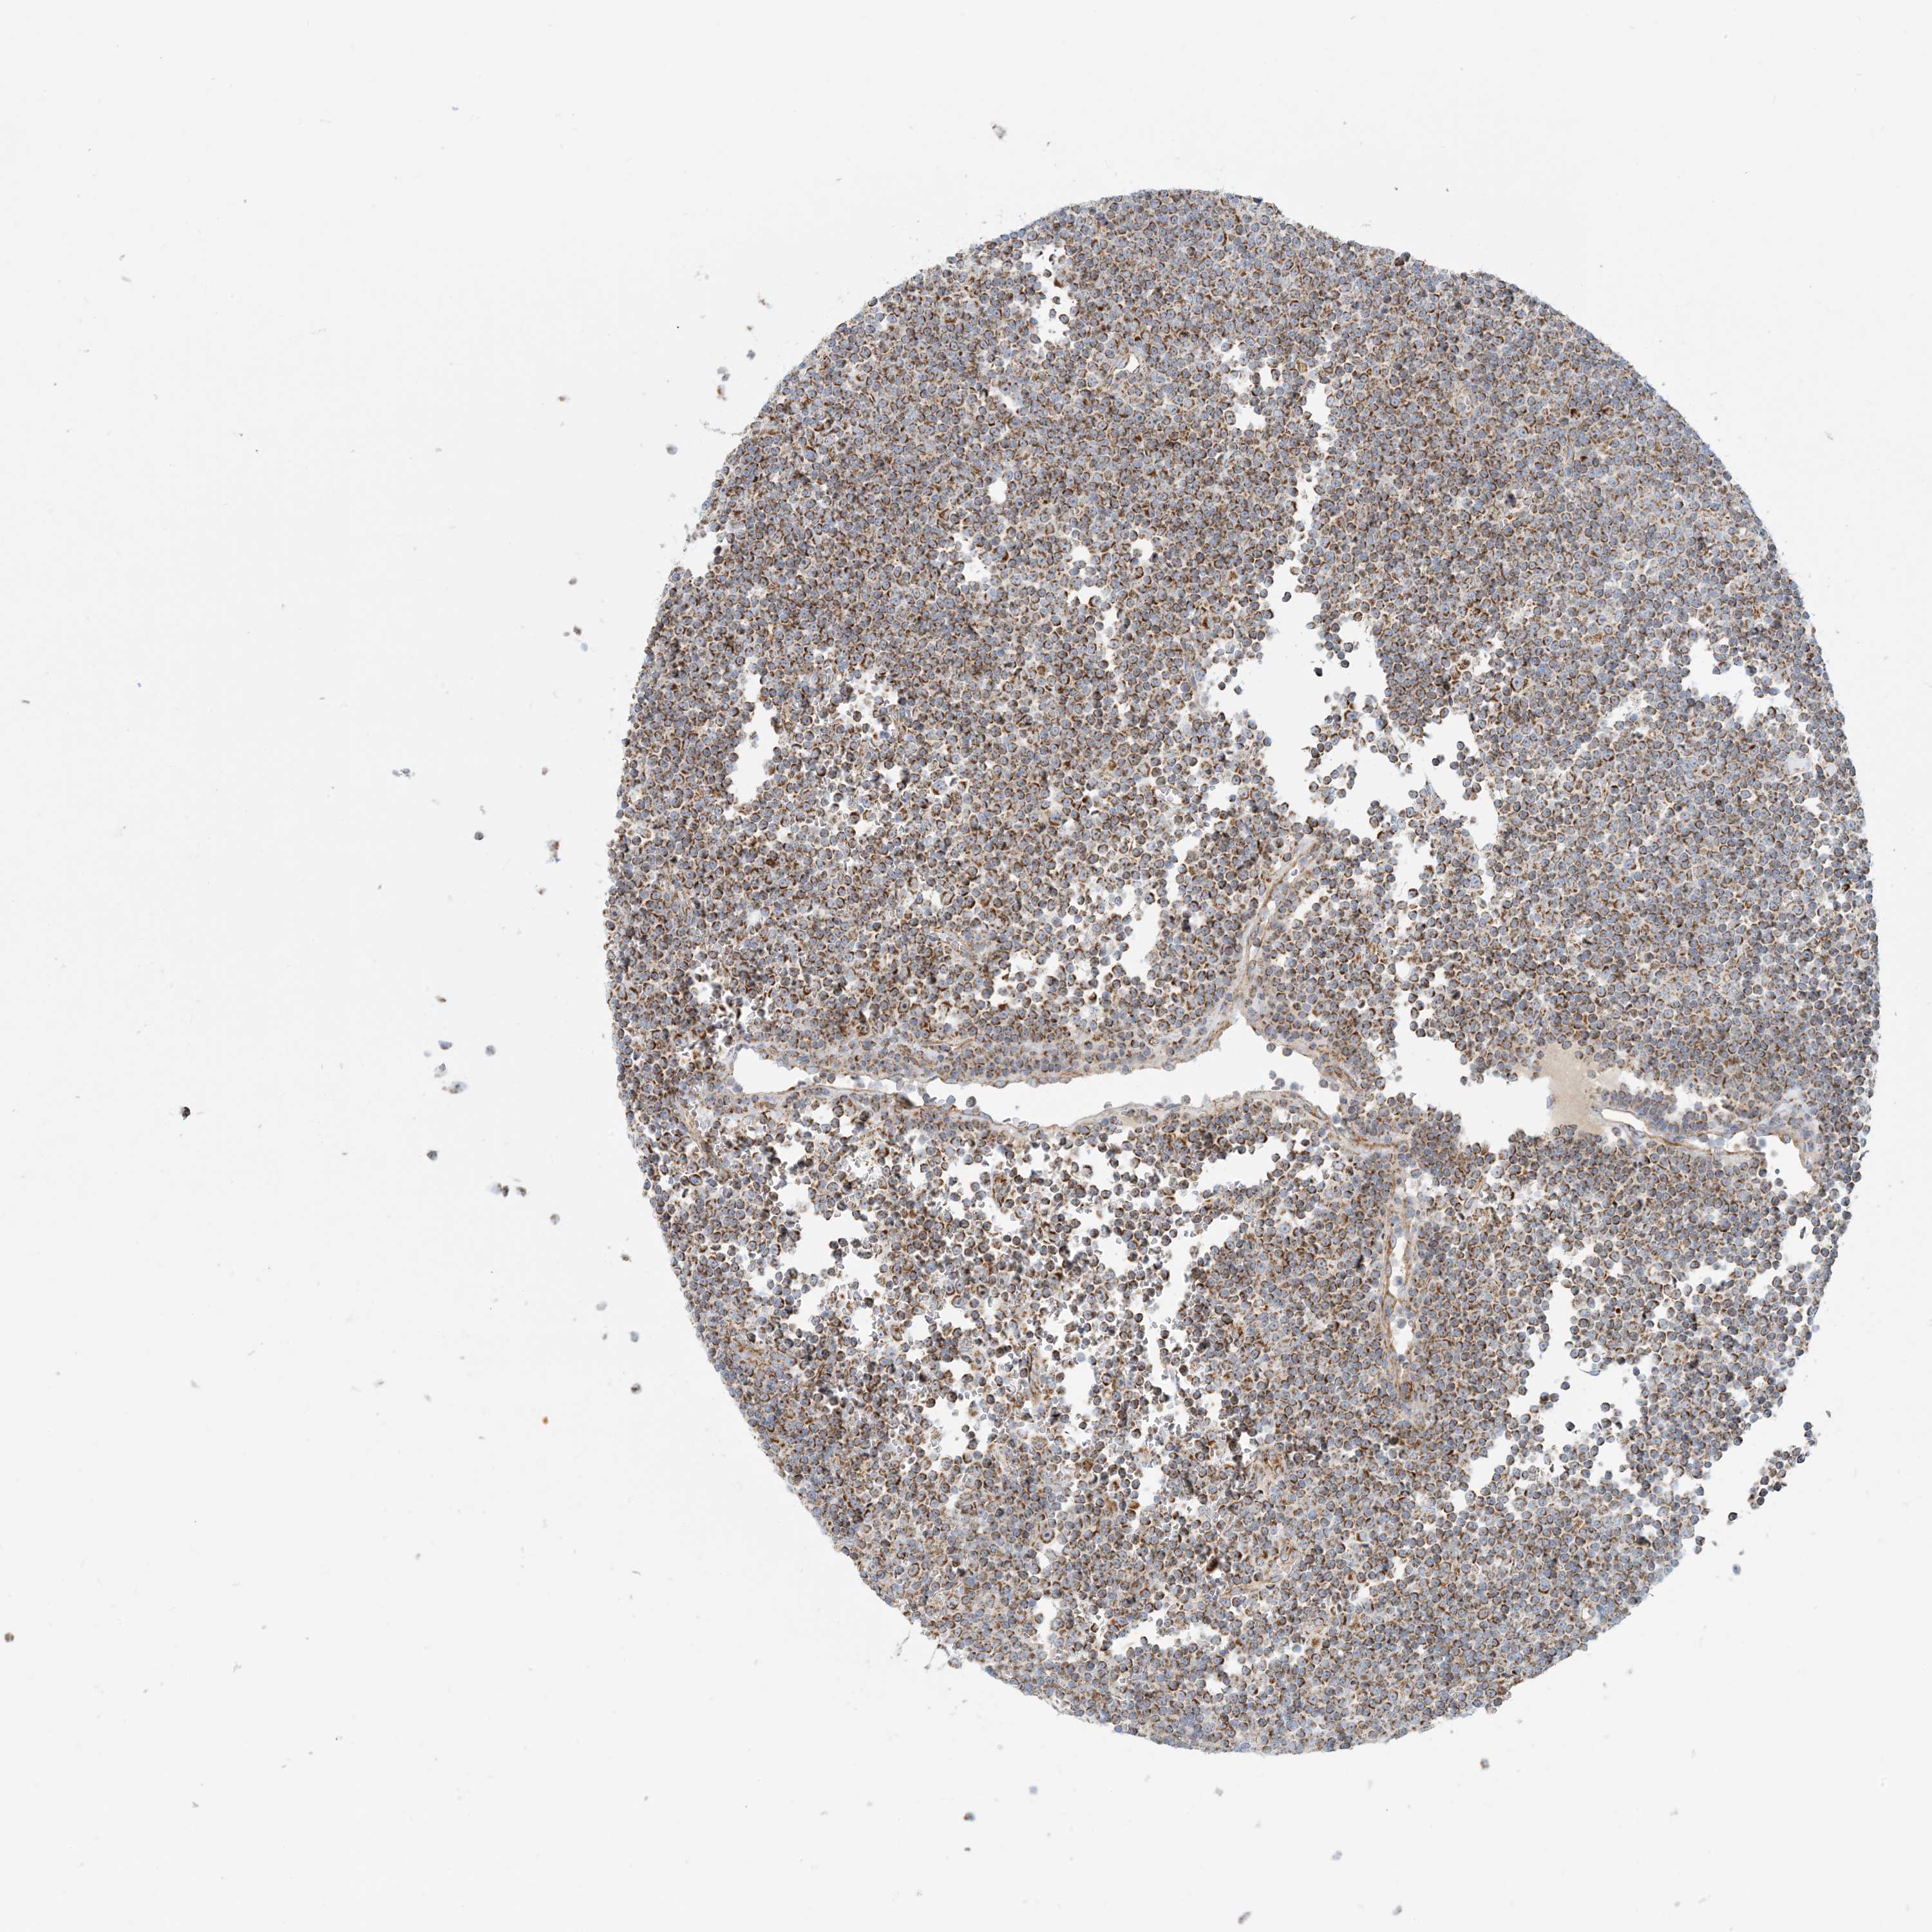

LYMPHOMA - Protein expressioni

A mouse-over function shows sample information and annotation data. Click on an image to view it in a full screen mode. Samples can be filtered based on level of antibody staining by selecting one or several of the following categories: high, medium, low and not detected. The assay and annotation is described here.

Each image is clickable and will lead to virtual microscopy that enables deeper exploration of all samples and also displays staining intensity scores, fraction scores and subcellular localization as well as patient and tissue information for each sample.

Antibody HPA031966

Staining

High

Medium

Intensity

Strong

Moderate

Quantity

>75%

75%-25%

Location

Nuclear

Cytoplasmic/membranous

Hodgkin's disease, NOS

Malignant lymphoma, non-Hodgkin's type, High grade

Malignant lymphoma, non-Hodgkin's type, Low grade